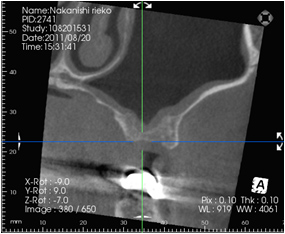

ガイデッド・サージェリーとは、CTで得られた情報を元に、

インプラント埋入のプランニングソフトで、より正確にシミュレーションを行い、

無切開無痛手術の安全性を更に向上させた手術方法です。